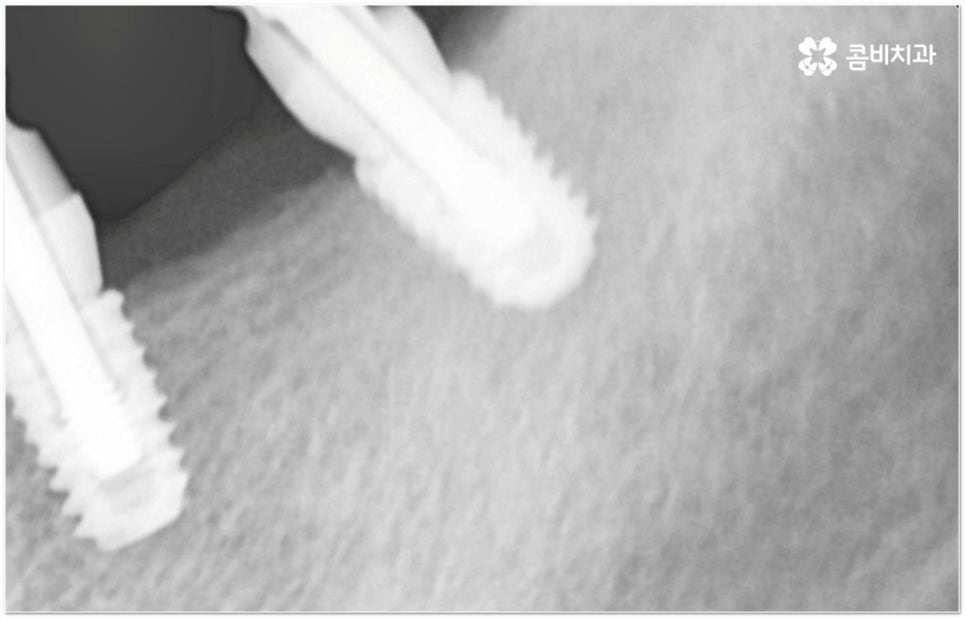

그러나 임플란트는 잇몸뼈에 직접 심어서 고정시키는 방식인 만큼 만약 환자분의 잇몸뼈가 부족하거나 치아가 빠진 후 오랜 시간이 지나 이미 잇몸뼈 소실이 상당 부분 이루어진 상태라고 한다면 먼저 골이식을 통해 이를 보충한 후 식립을 진행하는 뼈이식임플란트 방식을 이용할 필요가 있어요. 골이식 과정은 바탕이 되는 잇몸뼈의 밀도나 높이, 두께가 부족한 부분에 이식 재료를 심어주어 뼈를 재건해 주는 것인데 충분한 시간을 두고 무리하지 않게 진행하는 것이 뼈이식임플란트 수술의 성공률 및 안정적인 지속성을 높일 수 있는 방법이 될 거예요.

뼈이식임플란트 가 필요한지 살펴볼 때 3D CT 촬영과 같은 정밀 진단을 통해서 환자분의 잇몸뼈 두께 등 치조골 상태 뿐 만 아니라 구강 구조, 치아 및 잇몸 상태, 신경관 위치, 상악동까지의 거리 등을 꼼꼼하게 확인하여 치료 계획을 세우고 필요하다면 구강 질환에 대한 치료나 상악동 거상술 등을 선행하며 잇몸뼈 부족에 대해서도 골이식 과정을 먼저 진행하게 되는데요, 이러한 뼈이식임플란트 시술은 상당히 고난도의 복잡한 치과 진료인 만큼 관련 임상 경험이 풍부한 의료진과 함께 하는 것이 굉장히 중요하며 또한 수술 후 관리 면에서도 더욱 신경을 써 주시길 당부드리고 있어요.